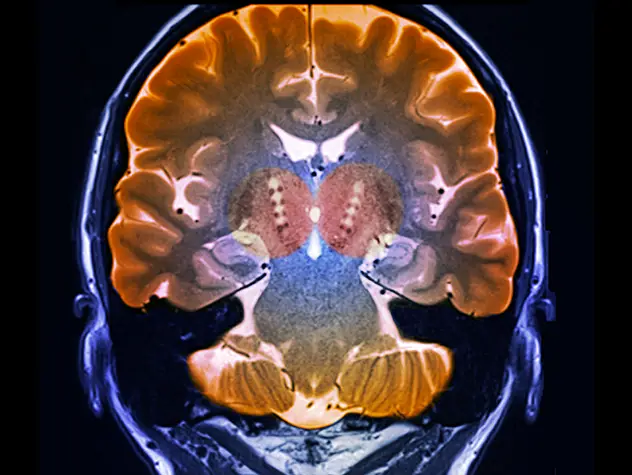

Innovative technologies and alternatives to traditional treatments are transforming the diagnosis and management of neurological conditions. In 2025, NewYork-Presbyterian physicians and surgeons from Columbia and Weill Cornell Medicine used sonication and convection-enhanced delivery to penetrate the blood-brain barrier, validated an adjunctive treatment for subdural hematoma, broadened access to spine surgery, advanced experimental therapies for neurodegenerative diseases, and more. Our specialists have been steadfast in reshaping the fields of neurology and neurosurgery in the pursuit of better patient outcomes and enhanced quality of care.

From cutting-edge research to compassionate patient practice, neurologists and neurosurgeons from Columbia and Weill Cornell Medicine are at the forefront of developing and applying the most advanced approaches to treat debilitating conditions affecting the brain and spine. With a broad range of focus on neurodegenerative and neurovascular disorders to malignant tumors, our innovative and advanced care is leading to new treatment options and enabling patients to achieve the best possible outcomes.